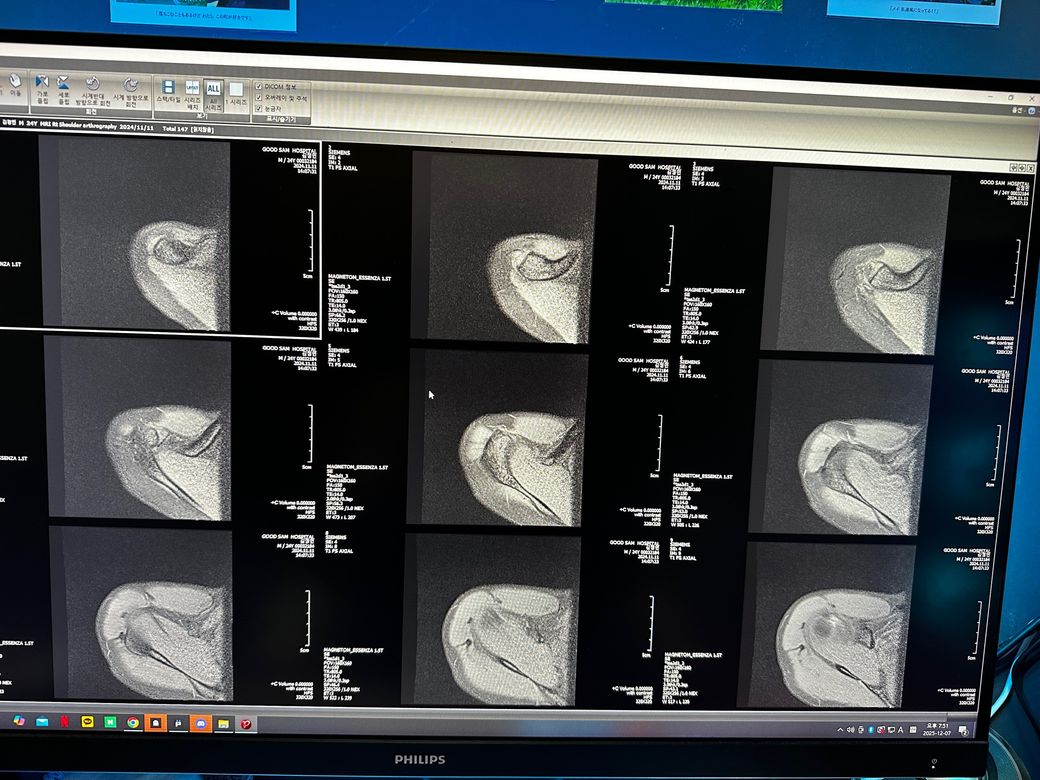

오른쪽어깨 관절mri좀 봐주세요 사진첨부입니다

오룬쪽어깨관절 엠알아이 결과좀 봐주세요

어떤가요

오룽쪽어꺄관절 엠알아이 결과지좀 봐주세요

오른쪽어깨관절부분입니다

관절입니다

• 1번 째 사진

• 2번 째 사진

• 3번 째 사진

조영제가 들어간 것으로 보이며, "회전근개(특히 극상근) 파열이나 큰 손상은 뚜렷하게 보이지 않는 편"입니다.

관절와순(Labrum) 주변에 조영제가 퍼져 보이지만, "명확한 파열 소견은 사진만으로 단정 어렵고 경미한 손상.염증 가능성"은 있습니다.

관절 안쪽에 "약한 염증/활액 증가"는 있어 보이며, 충돌증후군 초기 형태 가능성이 있습니다.